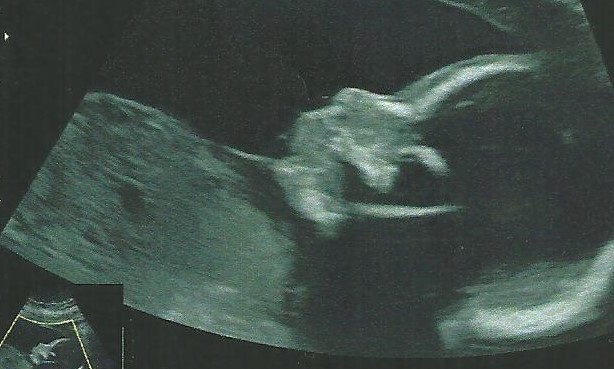

On recommence donc les injections et le suivi avec ponction ovocytaire, cette fois-ci 4 embryons sont viables. On décide avec mon conjoint d’en faire transférer deux. En sachant que les deux autres ne sont malheureusement pas congelables. Quinze jours plus tard le résultat de la prise de sang tombe : positif ! Nous sommes début avril 2017 soit 4 ans après le début de notre aventure, nous prenons toutes les précautions possibles pour ne pas revivre la même histoire qu’il y a un an et demi. A 5 semaines d’aménorrhées, l’échographie de contrôle nous révèle un embryon bien accroché et au bon endroit, les semaines passent et me voilà maintenant à 35 semaines. 4 ans de galère, de déception, et parfois de la souffrance pour enfin vivre notre rêve d’avoir un petit bout de nous. L’amour de notre couple n’en est que plus fort et il est grandi, sans mon conjoint je n’aurais sûrement pas tenu aussi longtemps, je le remercie pour ça, sa présence et son amour.